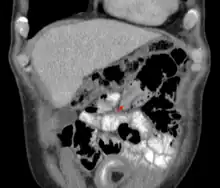

Intussusception

An intussusception as seen on CT

Small intestinal invagination on computed tomography

An intussusception is often suspected based on history and physical exam, including observation of Dance's sign. A digital rectal examination is particularly helpful in children, as part of the intussusceptum may be felt by the finger. A definite diagnosis often requires confirmation by diagnostic imaging modalities. Ultrasound is the imaging modality of choice for diagnosis and exclusion of intussusception, due to its high accuracy and lack of radiation. The appearance of target sign (also called "doughnut sign" on a sonograph, usually around 3 cm in diameter, confirms the diagnosis. The image seen on transverse sonography or computed tomography is that of a doughnut shape, created by the hyperechoic central core of bowel and mesentery surrounded by the hypoechoic outer edematous bowel.[11] In longitudinal imaging, intussusception resembles a sandwich.[11] It is also called "pseudokidney" sign because hyperechoic tubular centre is covered by a hypoechoic rim producing a kidney-like appearance.[12]